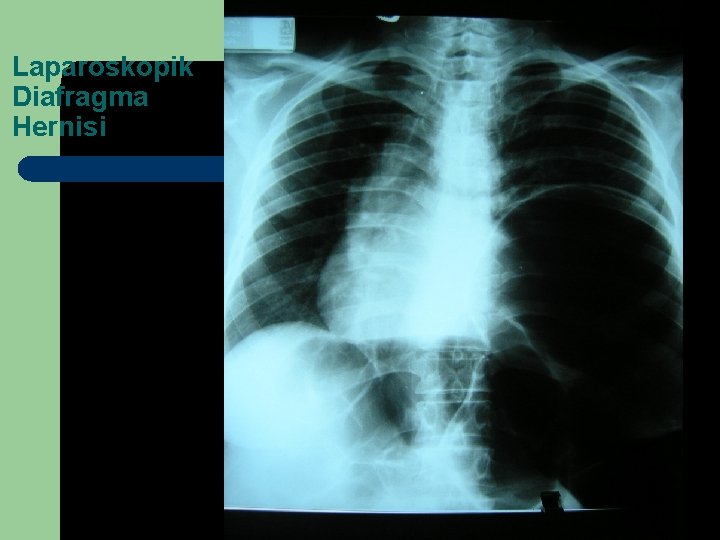

Laparoskopik Diafragma Hernisi